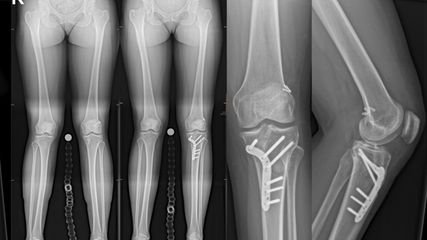

Angeborene Fehlstellungen des Unterschenkels

Kongenitale Deformitäten des Unterschenkels gehören zu den seltenen, aber medizinisch bedeutenden und operativ herausfordernden Diagnosen der Kinderorthopädie. Eine differenzierte ...